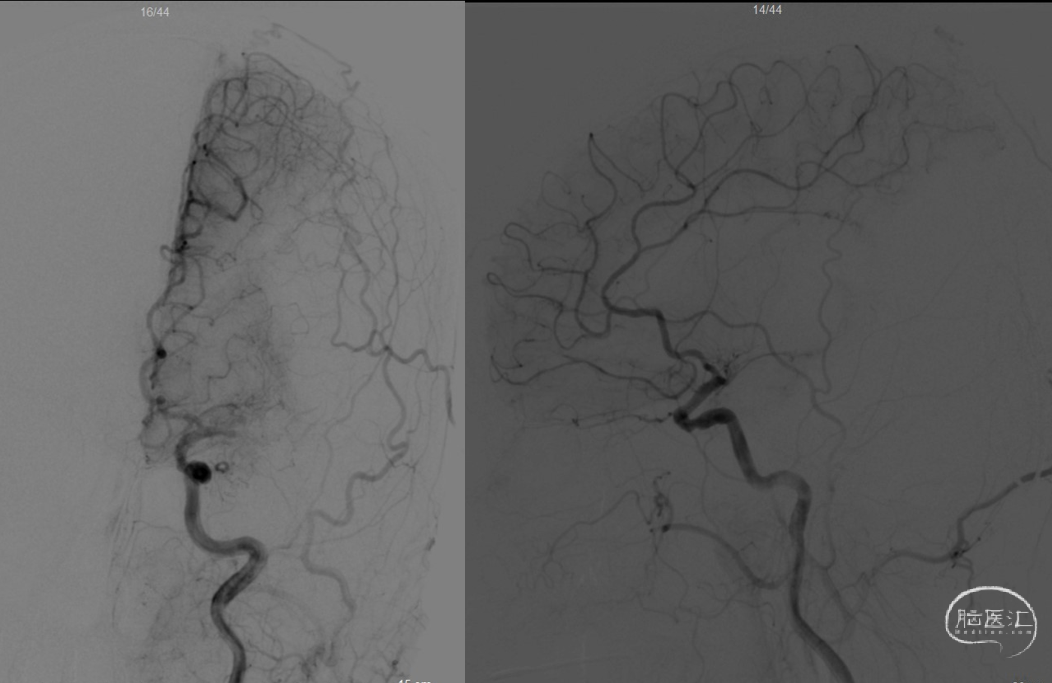

麻醉满意后,造影明确患者为Ⅲ型弓,血管迂曲,行左侧锁骨下造影示:左侧椎动脉开口处轻度狭窄,狭窄率约30%,超选入左椎动脉,造影示:左椎动脉及基底动脉走形正常,基底动脉、双侧大脑后动脉及小脑上动脉通畅,走形正常,前向血流TICI 3级。左颈总动脉及左侧颈内动脉走形正常,左侧大脑中动脉M1闭塞。撤出造影管。

术中DSA:左侧颈内动脉正侧位,M1闭塞